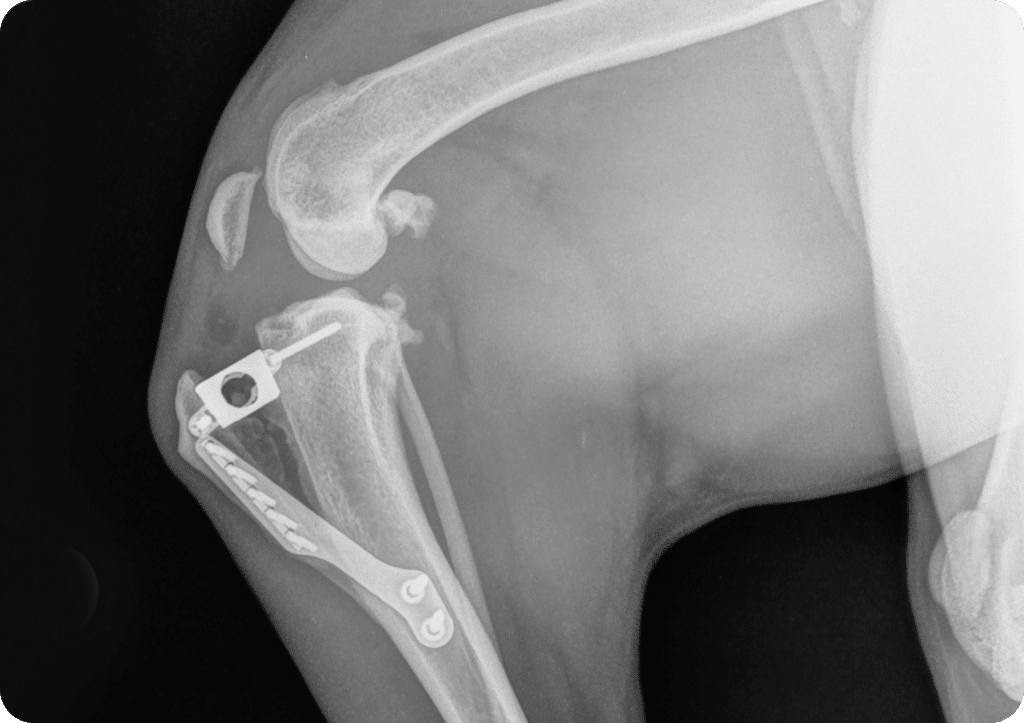

Tibial Tuberosity Advancement Surgery (TTA)

Tibial Tuberosity Advancement Surgery (TTA)Surgery to repair cranial cruciate rupture

At Sydney Animal Hospitals we offer a Tibial Tuberosity Advancement Surgery ‘TTA’ procedure to surgically restore function after cranial cruciate ligament rupture. The procedure is suitable for larger and more active dogs, with either a full rupture or partial cruciate tear.

The TTA procedure advances the tibial crest, to stabilize the knee joint and is suitable for most patients from 5kg and above.

The TTA surgery usually takes 60-90 minutes. The approach is to the medial (inside) of the stifle joint and the incision is in this area. The osteotomies are made with an oscillating saw and once the corrections are made a TTA rapid cage is inserted into the tibial crest osteotomy. The wound is closed in several layers and the skin sutured. We generally place a bandage and dressing over the surgical site. Patients are given intra operative IV antibiotics and pain medication. An iv analgesic infusion is continued for 24 hours post op, as well as oral antibiotics, anti-inflammatory and analgesic medications.